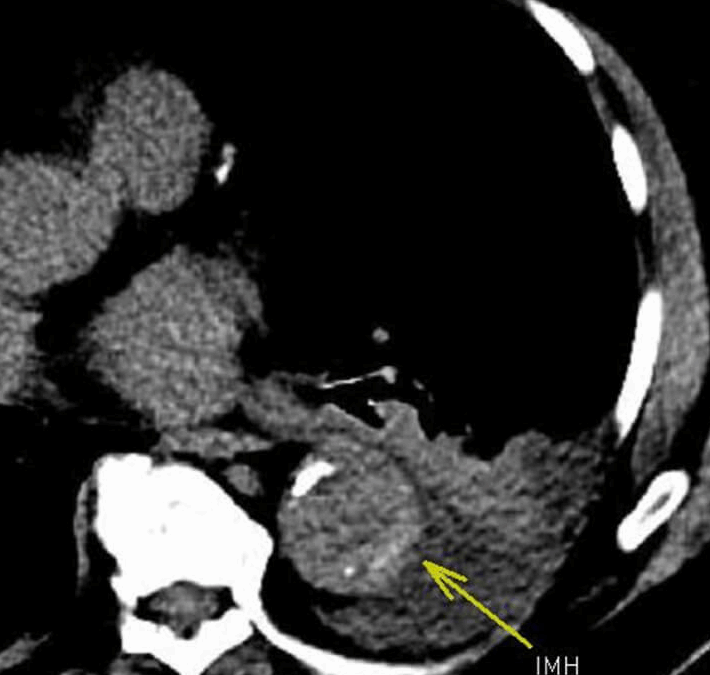

NEW: IgG4 Coronary Disease 73-year-old male with chest pain and elevated inflammatory markers suggesting possible vasculitis. History of prior coronary artery stenting. Figure A. Coronal MPR image from coronary computed tomography angiography (CCTA) shows marked mural...